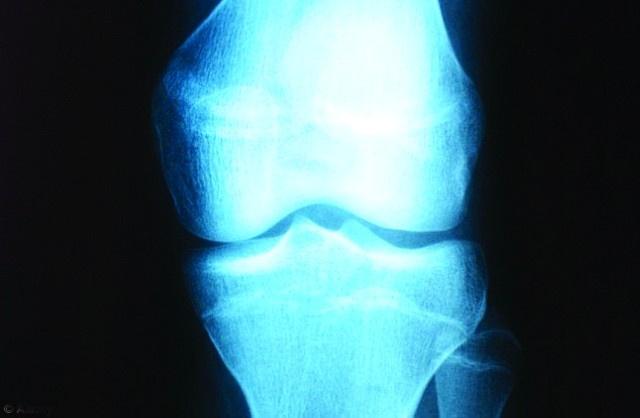

حقق الباحثون في جامعة بريستول البريطانية، أخيرا، إنجازا كبيرا في سعيهم الدؤوب لاستبدال الوركين والركبتين لتحل محلها أعضاء طبيعية يتم إنماؤها مخبريا.

وقد اكتشف الباحثون البريطانيون وسيلة للتغلب على معوق رئيسي يتعلق بتنمية تراكيب غضروفية كبيرة الحجم، ويتمثل ذلك بتزويد الخلايا الجذعية المهندسة في الجسم باحتياطي من الأكسجين.

وذكرت صحيفة "ديلي ميل" البريطانية أن الهدف النهائي لهذه الدراسة هو تمكن الباحثين من استبدال التراكيب المعقدة في الجسم لتحل محلها أخرى سليمة، نتيجة الإصابة بالتهاب المفاصل أو في حوادث السيارات.

وسيساعد هذا الانجاز كذلك على تنمية أعضاء سليمة كالعظام وعضلة القلب لاستبدال الأجزاء المتضررة بها.